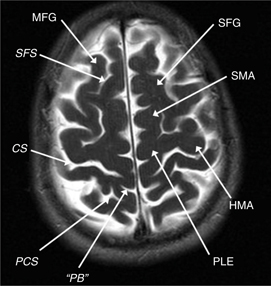

The frontal lobe contains three gyri (superior, middle, inferior) separated by the superior and inferior frontal sulci. The superior frontal gyrus is appreciated on both axial and sagittal images (Figure 1). The middle frontal gyrus (MFG) extends posteriorly and fuses with the vertically oriented precentral gyrus. The precentral sulcus starts at midline and extends anteriorly and laterally in an oblique direction. The next key finding is the merging of the inferior frontal sulcus with the inferior ramus of the precentral sulcus, forming a “T” shape (4, 5). More posteriorly, the central sulcus is identified over the convexity on axial or sagittal images. It is oriented obliquely from posterior to anterior and does not extend all the way into the Sylvian fissure. Inferiorly, the precentral gyrus and postcentral gyrus merge under the central sulcus through a “U”-shaped gyrus (the subcentral gyrus). The post-central gyrus is characteristically narrower than the precentral gyrus (4, 5). Posteriorly, the Sylvian fissure is capped by the SMG, which is the anterior most portion of the inferior parietal lobule. Inferiorly, within the temporal lobe, coursing in parallel with the Sylvian fissure, is the superior temporal sulcus, which is capped posteriorly by the angular gyrus, the posterior limit of the inferior parietal lobule. The angular gyrus (Brodmann’s area 39) and posterior aspect of the superior temporal gyrus (STG) (Brodmann’s area 22) represent the primary receptive speech area (Wernicke’s area). The SMG (Brodmann’s area 40) contains fibers from the arcuate fasciculus that connect Wernicke’s and Broca’s areas (4, 5). The cingulate sulcus separates the cingulate gyrus from the medial aspect of the superior frontal gyrus. If followed posteriorly, the cingulate sulcus angles superiorly to form the pars marginalis, marking the posterior aspect of the paracentral lobule. The paracentral lobule houses the central sulcus, Broadman Areas 3,1,2 and 4,6. On axial images, the pars marginalis may be appreciated as a “bracket” (pars bracket) extending symmetrically from midline left and right. Anterior to this are the primary motor cortex and the postcentral sulcus. Areas 3,1,2 relate to the primary sensory cortex, and areas 4,6 include primary motor and supplemental motor areas (4, 5) (Figures 1 and 2).

Fig 1

Figure 1 Axial T2-weighted MRI showing the middle frontal gyrus (MFG), superior frontal gyrus (SFG), superior frontal sulcus (SFS), central sulcus (CS), supplementary motor area (SMA), postcentral sulcus (PCS), pars bracket (PB), hand motor area (HMA), and proximal leg area (PLE).